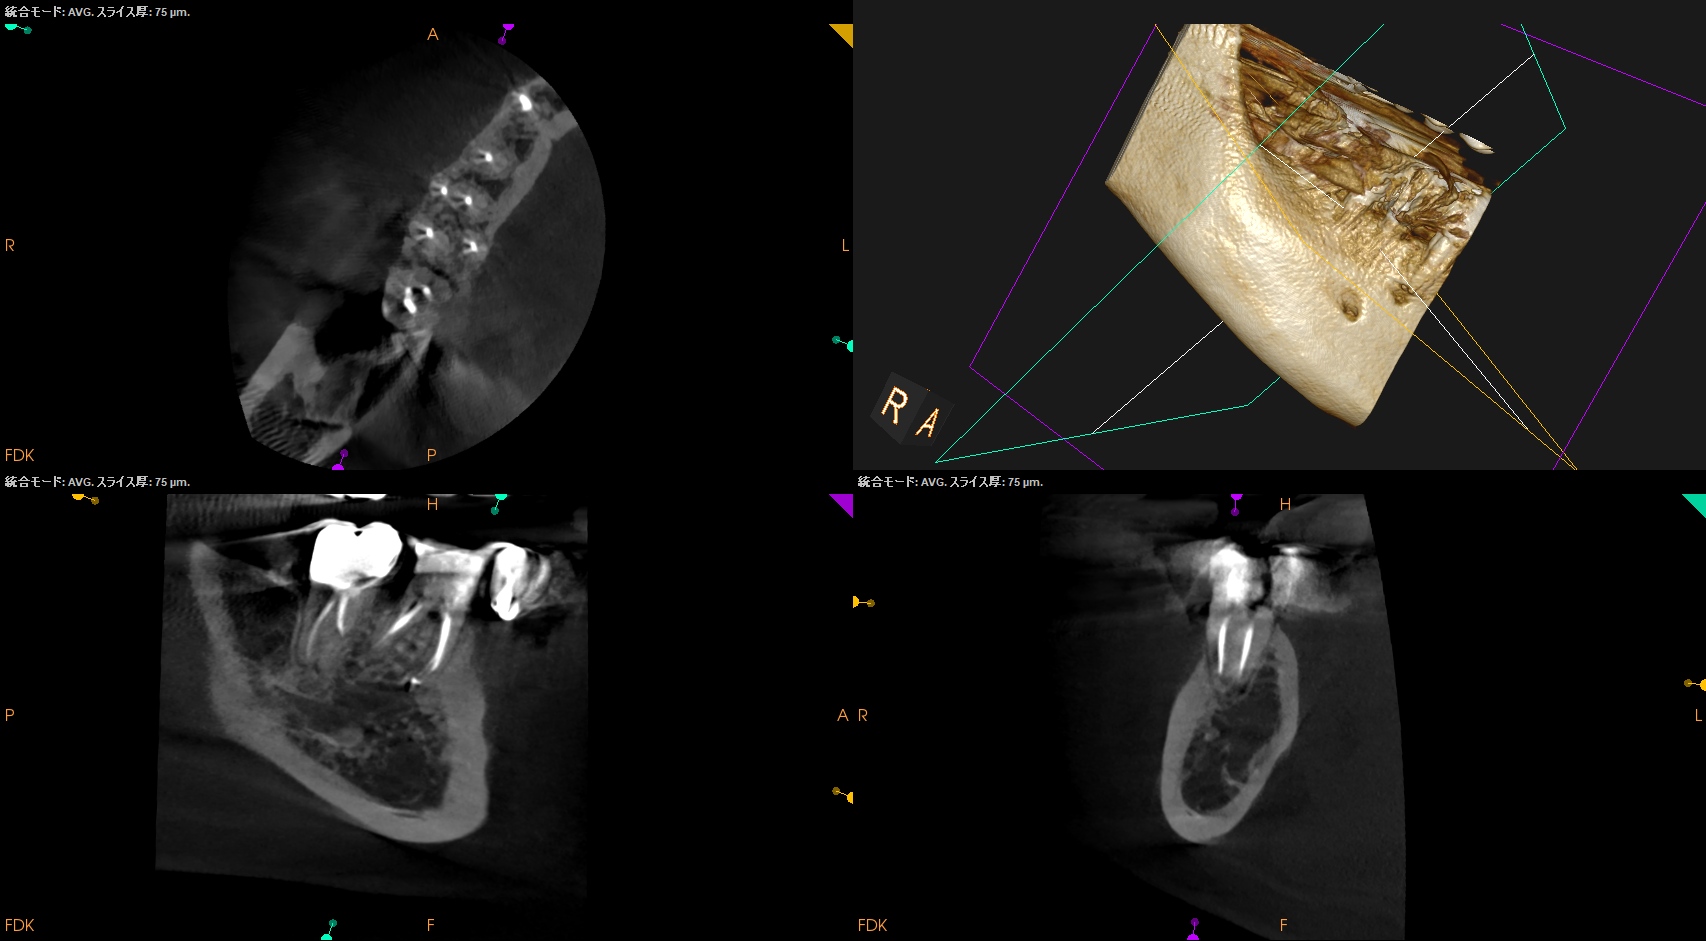

Pre-op Endo test(2026.3.11)

MB

ML

D

Radix

Gold Inlayの封鎖性を持ってしても歯髄の生活性を担保することはできなかったようだ。

ということでRadix以外の根管全てに根尖病変があり、穿通がマストだ。

が、歯髄に近い修復で石灰化が進んでいる。

SXを入れる前に短針でスカウティングが必要だろう。

またRadixも湾曲が強い。

ここも形成で工夫が必要だ。

Pulp Dx: Pulp Necrosis

Periapical Dx: Symptomatic apical periodontitis

Recommended Tx: RCT